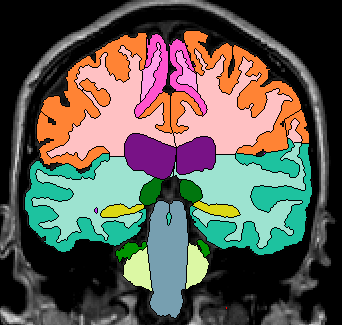

Because proper segmentation of the cerebral exterior includes a clearly drawn in Sylvian Fissure, segmentation of the insula in the more posterior coronal slices is simply a matter of “extending” these drawn in lines to the medial white matter (Fig 4-5)

Figure 4                  Figure

5